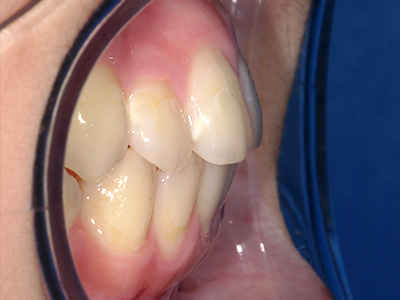

ないき歯科クリニックでは、これからあごが成長していくお子様や、歯並びが気になる成人の方など、さまざまな年代の方に対して矯正治療を行っています。

歯並びやかみ合わせを正しく整えると、笑顔や発音の自信につながり、むし歯・歯周病・口臭の予防にも役立ちます。

矯正装置を装着し、調整しながら少しずつ歯を移動させ、歯並びを整えていきます。